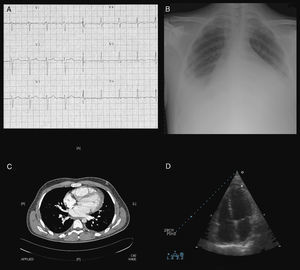

En las pruebas de laboratorio, hemoglobina 9,3g/dl, leucocitos 33.200/mm3 (neutrófilos 93,8%), plaquetas 512.000/mm3, actividad de protrombina 51,9%, GOT 177 U/l, GPT 108 U/l, gammaglutamil transpeptidasa 225 U/l, LDH 1.044 U/l y troponina I 3 ng/ml. Proteína C reactiva 262,8mg/l, velocidad de sedimentación globular 97mm/1.a hora y ferritina 37.640 ng/ml. Hormonas tiroideas, inmunoglobulinas y complemento normales. Factor reumatoide, ANA, antígeno nuclear extraíble, anti-ADNn, anticuerpos citoplasmáticos antineutrófilos y antifosfolípidos, negativos. Serologías, hemocultivos, urocultivos y Mantoux, negativos. Frotis sin hallazgos. Gasometría arterial, insuficiencia respiratoria parcial. Electrocardiograma, taquicardia sinusal con T negativas en V4-6 (fig. 1A). En radiografía de tórax (fig. 1B), cardiomegalia global y derrame pleural bilateral. Líquido pleural tipo exudado, con baciloscopias, cultivos y citología negativos. En la TC toraco-abdominal (fig. 1C), mínimo derrame pleuropericárdico, cardiomegalia y hepatomegalia. En el ecocardiograma (fig. 1D), derrame pericárdico leve-moderado, fracción de eyección del ventrículo izquierdo 41%, insuficiencia mitral moderada-severa y estenosis mitral leve-moderada.

Estudios de apoyo paraclínico que evidenciaron la presencia de miopericarditis: taquicardia sinusal y ondas T negativas en derivaciones V4-V6 del ECG (A), cardiomegalia global y derrame pleural bilateral en la radiografía de tórax (B), derrame pleuropericárdico y cardiomegalia en la TC toraco-abdominal (C), derrame pericárdico leve a moderado en el ecocardiograma (D).